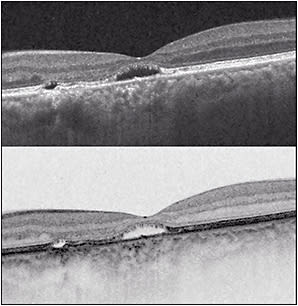

The natural history in the vast majority of CSC cases is spontaneous resolution within 2-3 months (so-called classic CSC). In these cases, central vision is minimally affected and usually returns to normal after reabsorption of the subretinal fluid (Figure 1). However, as many as 10% of all patients with CSC develop persistent serous macular detachment (chronic CSC or “diffuse retinal pigment epitheliopathy” [DRPE], lasting 3 months to 6 months or longer).10 In these DRPE cases, progressive and irreversible visual decline can be associated with the development of central RPE atrophy and (due to increased diffusion distance between the oxygenating and nourishing choriocapillaris, trophic RPE, and the photoreceptors) cystoid macular degeneration and foveal atrophy (Figures 2 and 3).11-15

Discontinuance of the steroid, if possible, will likely result in resolution of the episode. Specific treatment of CSC patients with Cushing syndrome (Figure 3) will also result in resolution of the CSC episode. Also, plasma cortisol levels are elevated during pregnancy, especially during the third trimester. When CSC is associated with pregnancy, resolution of the episode occurs spontaneously after childbirth.